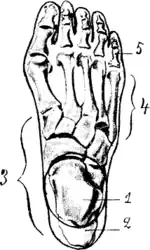

| Hallux not labeled but visible at upper left. | |